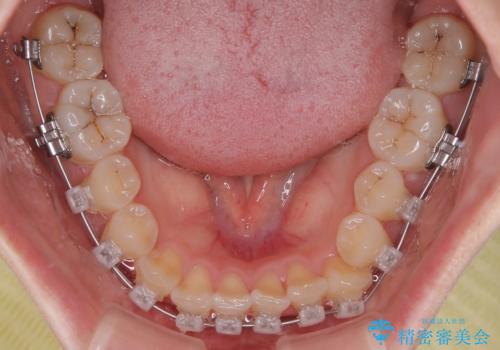

診察の結果、上下の前歯部に**叢生(そうせい/歯のガタガタ・重なり)**が認められました。

治療方法としては、装置の目立ちにくさと費用面のバランスを考慮して、プラスチック製のクリアブラケットとメタルワイヤーを組み合わせた矯正装置を使用することにしました。

矯正治療期間はわずか10か月と、比較的短期間で終了しました。

前歯のデコボコがなくなり、見た目の印象が大きく変わっただけでなく、歯磨きがしやすくなり、むし歯や歯周病のリスクが大きく減少しました。